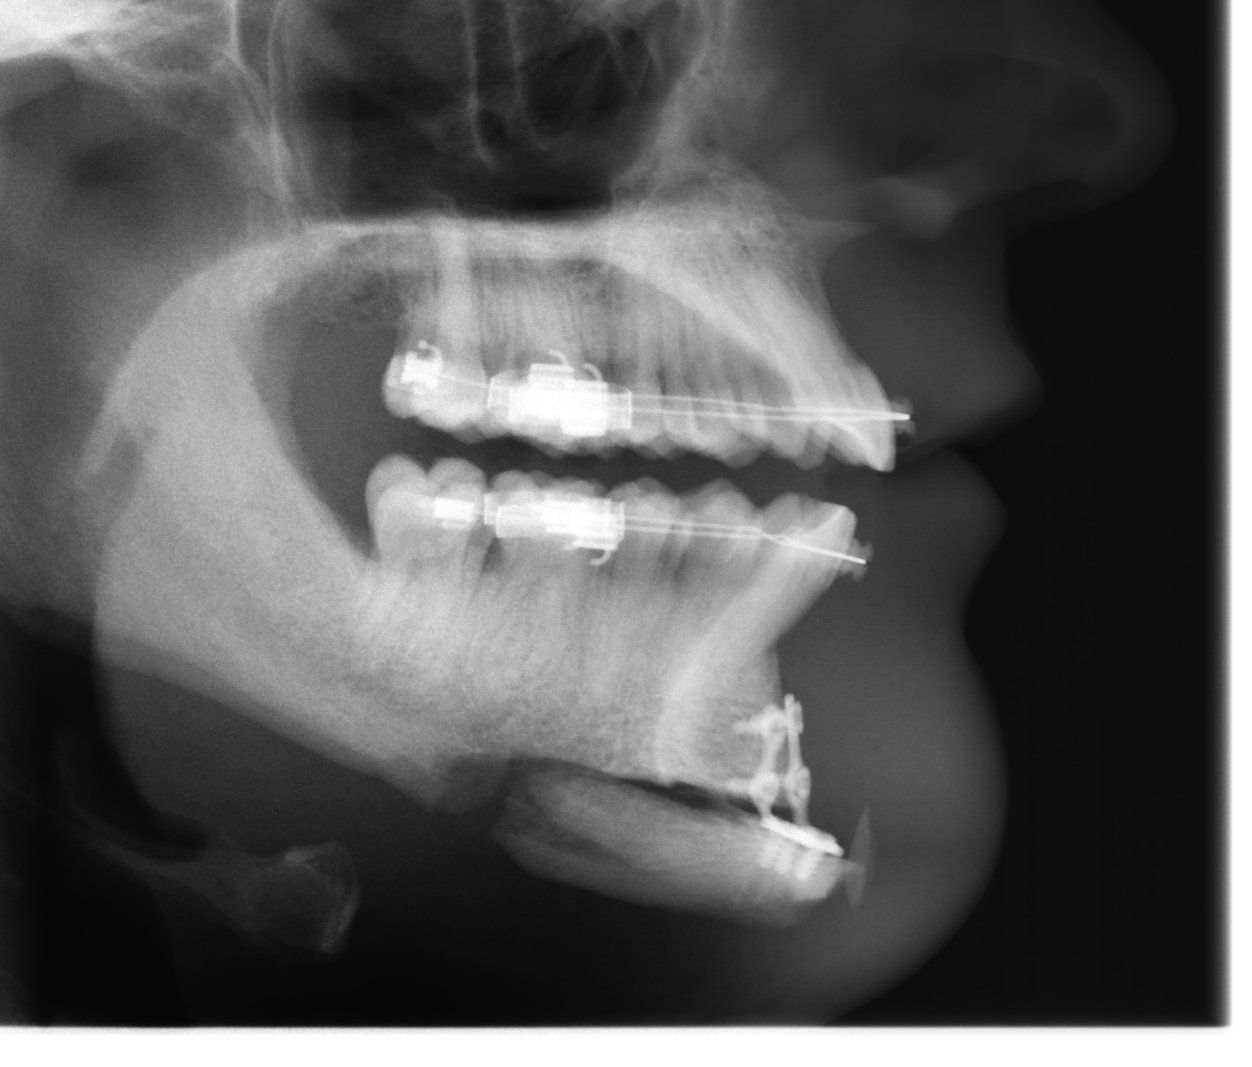

El hueso propio puede ser aserrado, movido y removido. El plástico se puede introducir e intercambiar. El acceso es a través de la incisión en la línea de las encías. La operación generalmente se realiza bajo anestesia. El coste de la operación incluyendo anestesia e IVA es de 1.799,00€.